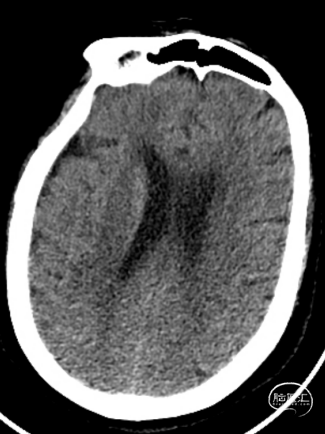

患者为急性脑梗死,头颅CT未见明显低密度病灶,CTA提示:右侧颈内动脉及右侧大脑中动脉M1段闭塞,远端分支减少,显影浅淡。目前患者神经功能缺损严重,有急诊取栓手术指征。

造影显示RICA:C1段起始部闭塞,残端呈锥形,TICI分级0级;RMCA未显影,远端由RACA经皮层支少量代偿,ASITN分级1-2级。

术后第一天复查颅脑CT未见异常染色及大面低密度病灶。

查头颅MRI:右侧基底节区、右侧顶颞岛叶急性脑梗死。